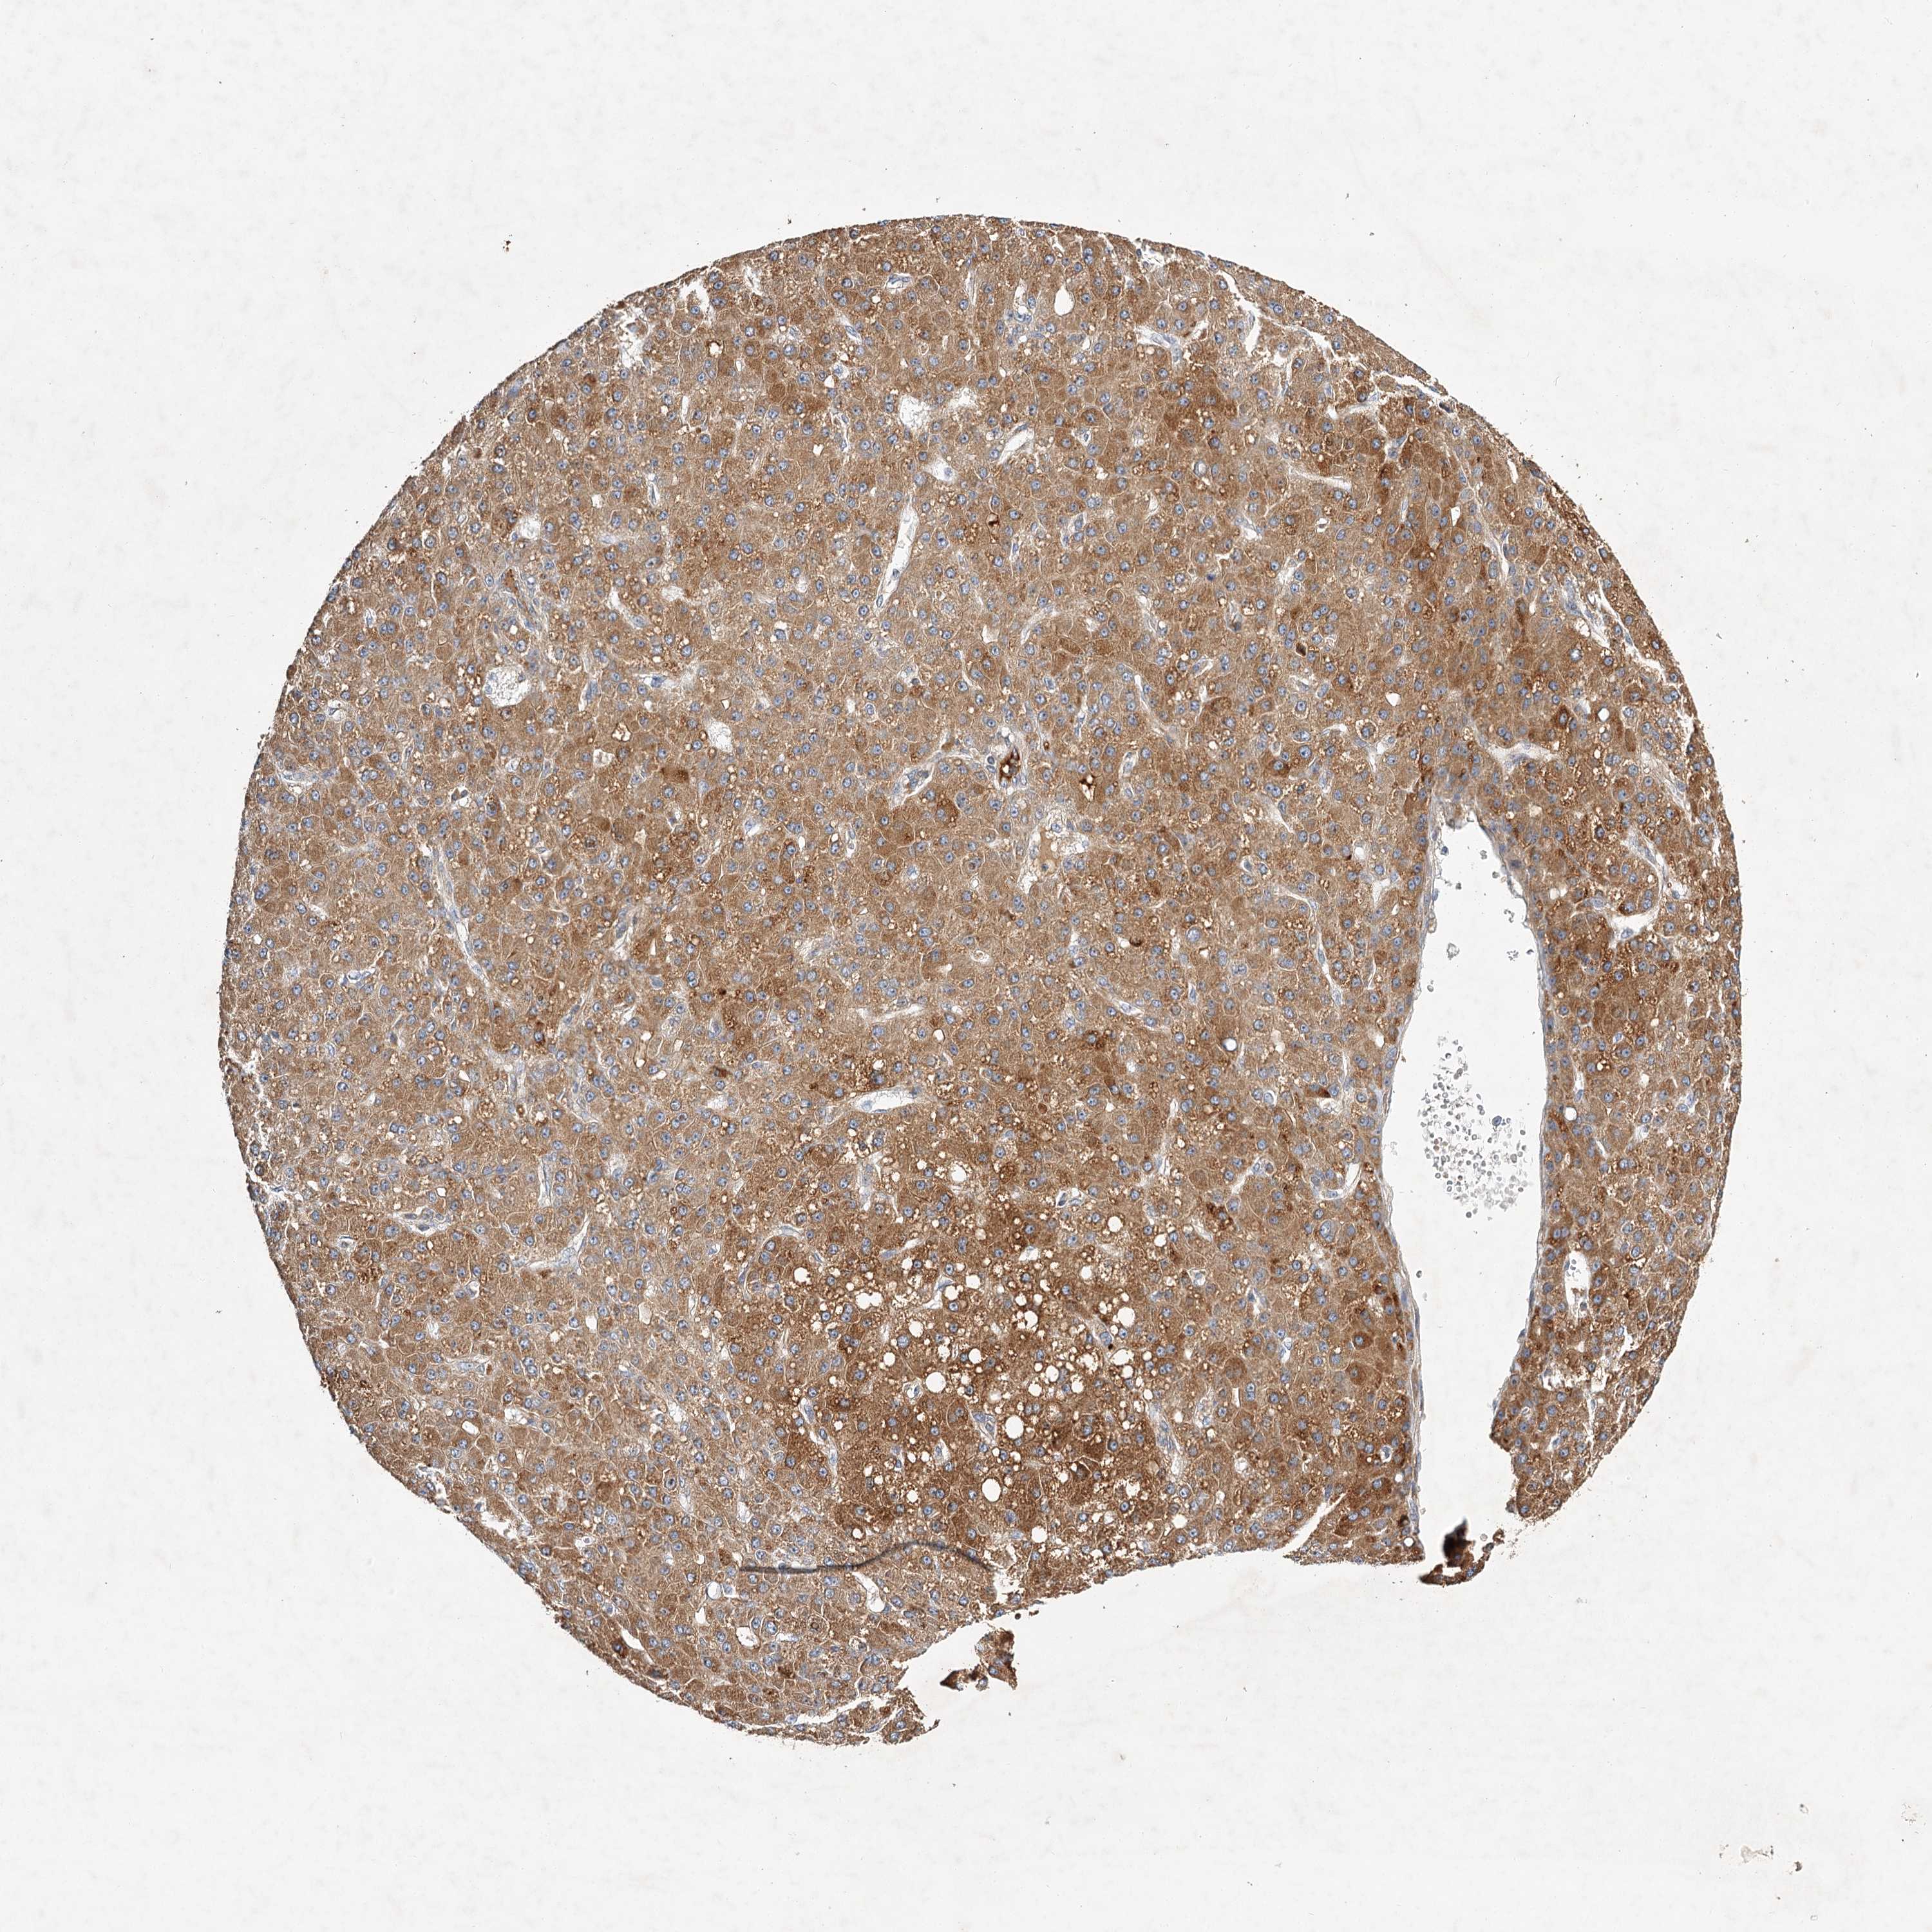

LIVER CANCER - Protein expressioni

A mouse-over function shows sample information and annotation data. Click on an image to view it in a full screen mode. Samples can be filtered based on level of antibody staining by selecting one or several of the following categories: high, medium, low and not detected. The assay and annotation is described here.

Note that samples used for immunohistochemistry by the Human Protein Atlas do not correspond to samples in the TCGA dataset.

Antibody stainingi

Antibody staining in the annotated cell types in the current human tissue is reported as not detected, low, medium, or high, based on conventional immunohistochemistry profiling in selected tissues. This score is based on the combination of the staining intensity and fraction of stained cells.

Each image is clickable and will lead to virtual microscopy that enables deeper exploration of all samples and also displays staining intensity scores, fraction scores and subcellular localization as well as patient and tissue information for each sample.

Antibody HPA032060

Antibody HPA032062

Antibody CAB034116

Staining

High

Medium

Low

Not detected

Intensity

Strong

Moderate

Weak

Negative

Quantity

>75%

75%-25%

<25%

None

Location

Nuclear

Cytoplasmic/membranous

Cytoplasmic/membranous,nuclear

Cholangiocarcinoma

Carcinoma, Hepatocellular, NOS